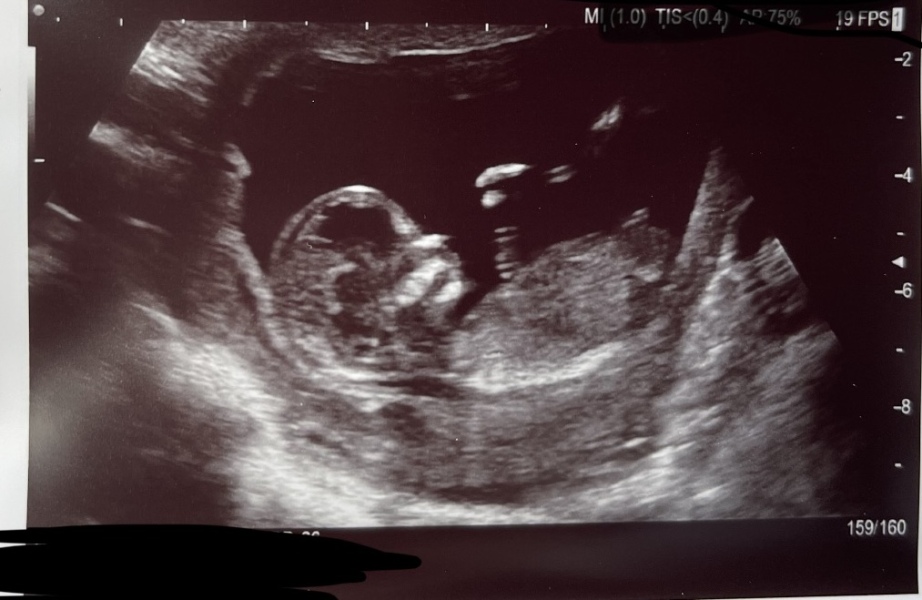

Any guesses for mine I find out tomorrow 🥰

Nub theory prediction wrong?

@nsb I think girl! Did you find out?

Nsb · 29/07/2023 15:34

ColleenRua · 29/07/2023 14:08

Most people did! And it was a baby boy! Don’t fall for nub theory it’s not always what you think! X